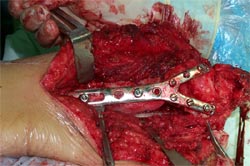

肱骨骨不连的骨断端多有硬化而骨干骨质疏松、遗留有以往手术的钢板、

钉孔,骨吸收骨干变细有严重骨缺损,治疗困难较大。

带锁髓内钉内固定,解决骨质疏松、骨干变细和骨缺损等情况

下的固定问题,进行复合骨髓细胞的植骨,促进骨折愈合